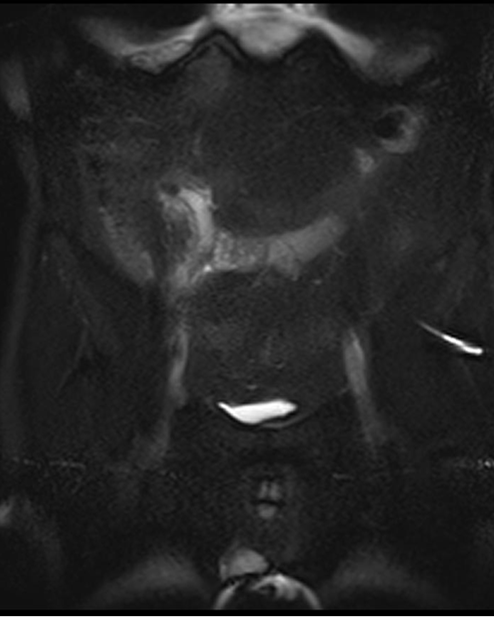

- KT yüksək həssaslıq və spesifiklik (95%) göstərir, diaqnostik çətinlikdə istifadə edilir. Genişlənmiş (diametri 6 mm-dən çox), divarı qalınlaşmış appendiks, ətrafında ödem, abses, fleqmona kimi əlamətlər appendisitə xarakterikdir (Şəkil 2).

- MRT nəticələri KT ilə eynidir, hamilə qadınlarda diaqnostik çətinlik olarsa istifadə edilir.

Şəkil 2. Appendisitin diaqnostikası